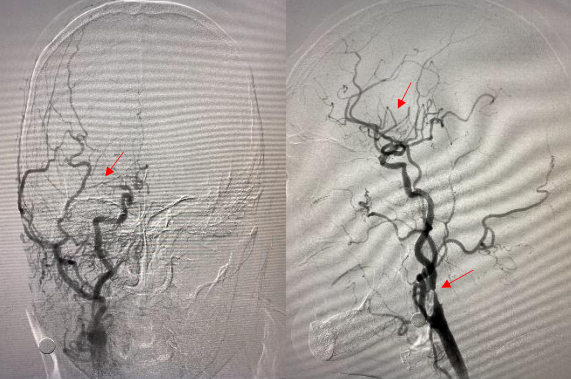

头颈部血管造影提示:患者为右侧颈内动脉极重度狭窄合并右侧大脑中动脉闭塞。

由远及近,优先开通右侧大脑中动脉恢复颅内血流,再行右侧颈内动脉起始部支架植入血管成形,顺利开通闭塞血管,颅内血流恢复。